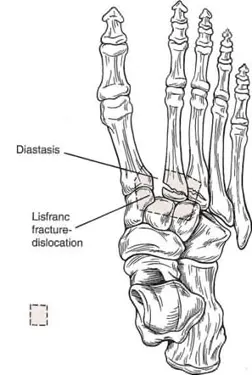

C1. Lisfranc injury

2nd metatarsal base fx.는 Lisfranc lig. complex의 disruption을 의미

Lisfranc injury의 기전, 진단, 치료에서의 가장 중요한 점은 2nd memtatarsal과 Lisfranc lig.이다.

(2) Unstable Lisfranc injury

X-ray에서 1st와 2nd metatarsal의 기저부 간격이 1㎜ 이상으로 벌어졌을 때

Unstable한 injury는 anatomic reduction해야 한다.

Compartment syndrome이 발생할 수 있다.